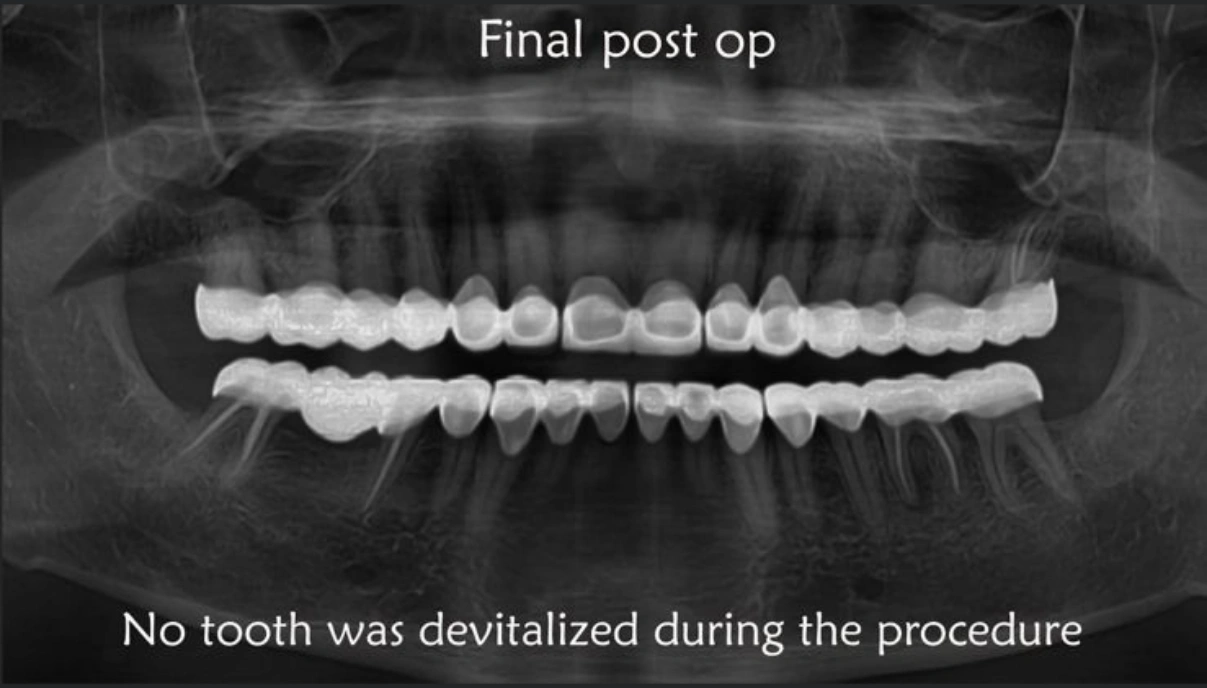

Full mouth rehabilitation includes restoration of lost tooth structure and bite. This technique sensitive procedure involves buildup of lost tooth enamel and dentin. Missing tooth can be replaced with Dental Implants or dental bridges. A Full mouth Reconstruction procedure is mainly indicated for patients with extreme tooth wear.

Full mouth rehabilitation (FMR) is a treatment plan for restoring function and function tolerance of dentition after surgery or dental restoration. It aims to restore dentition to the optimal point of function and esthetics of a healthy mouth. The treatment plan provides patients with a permanent smile that looks natural and bright.